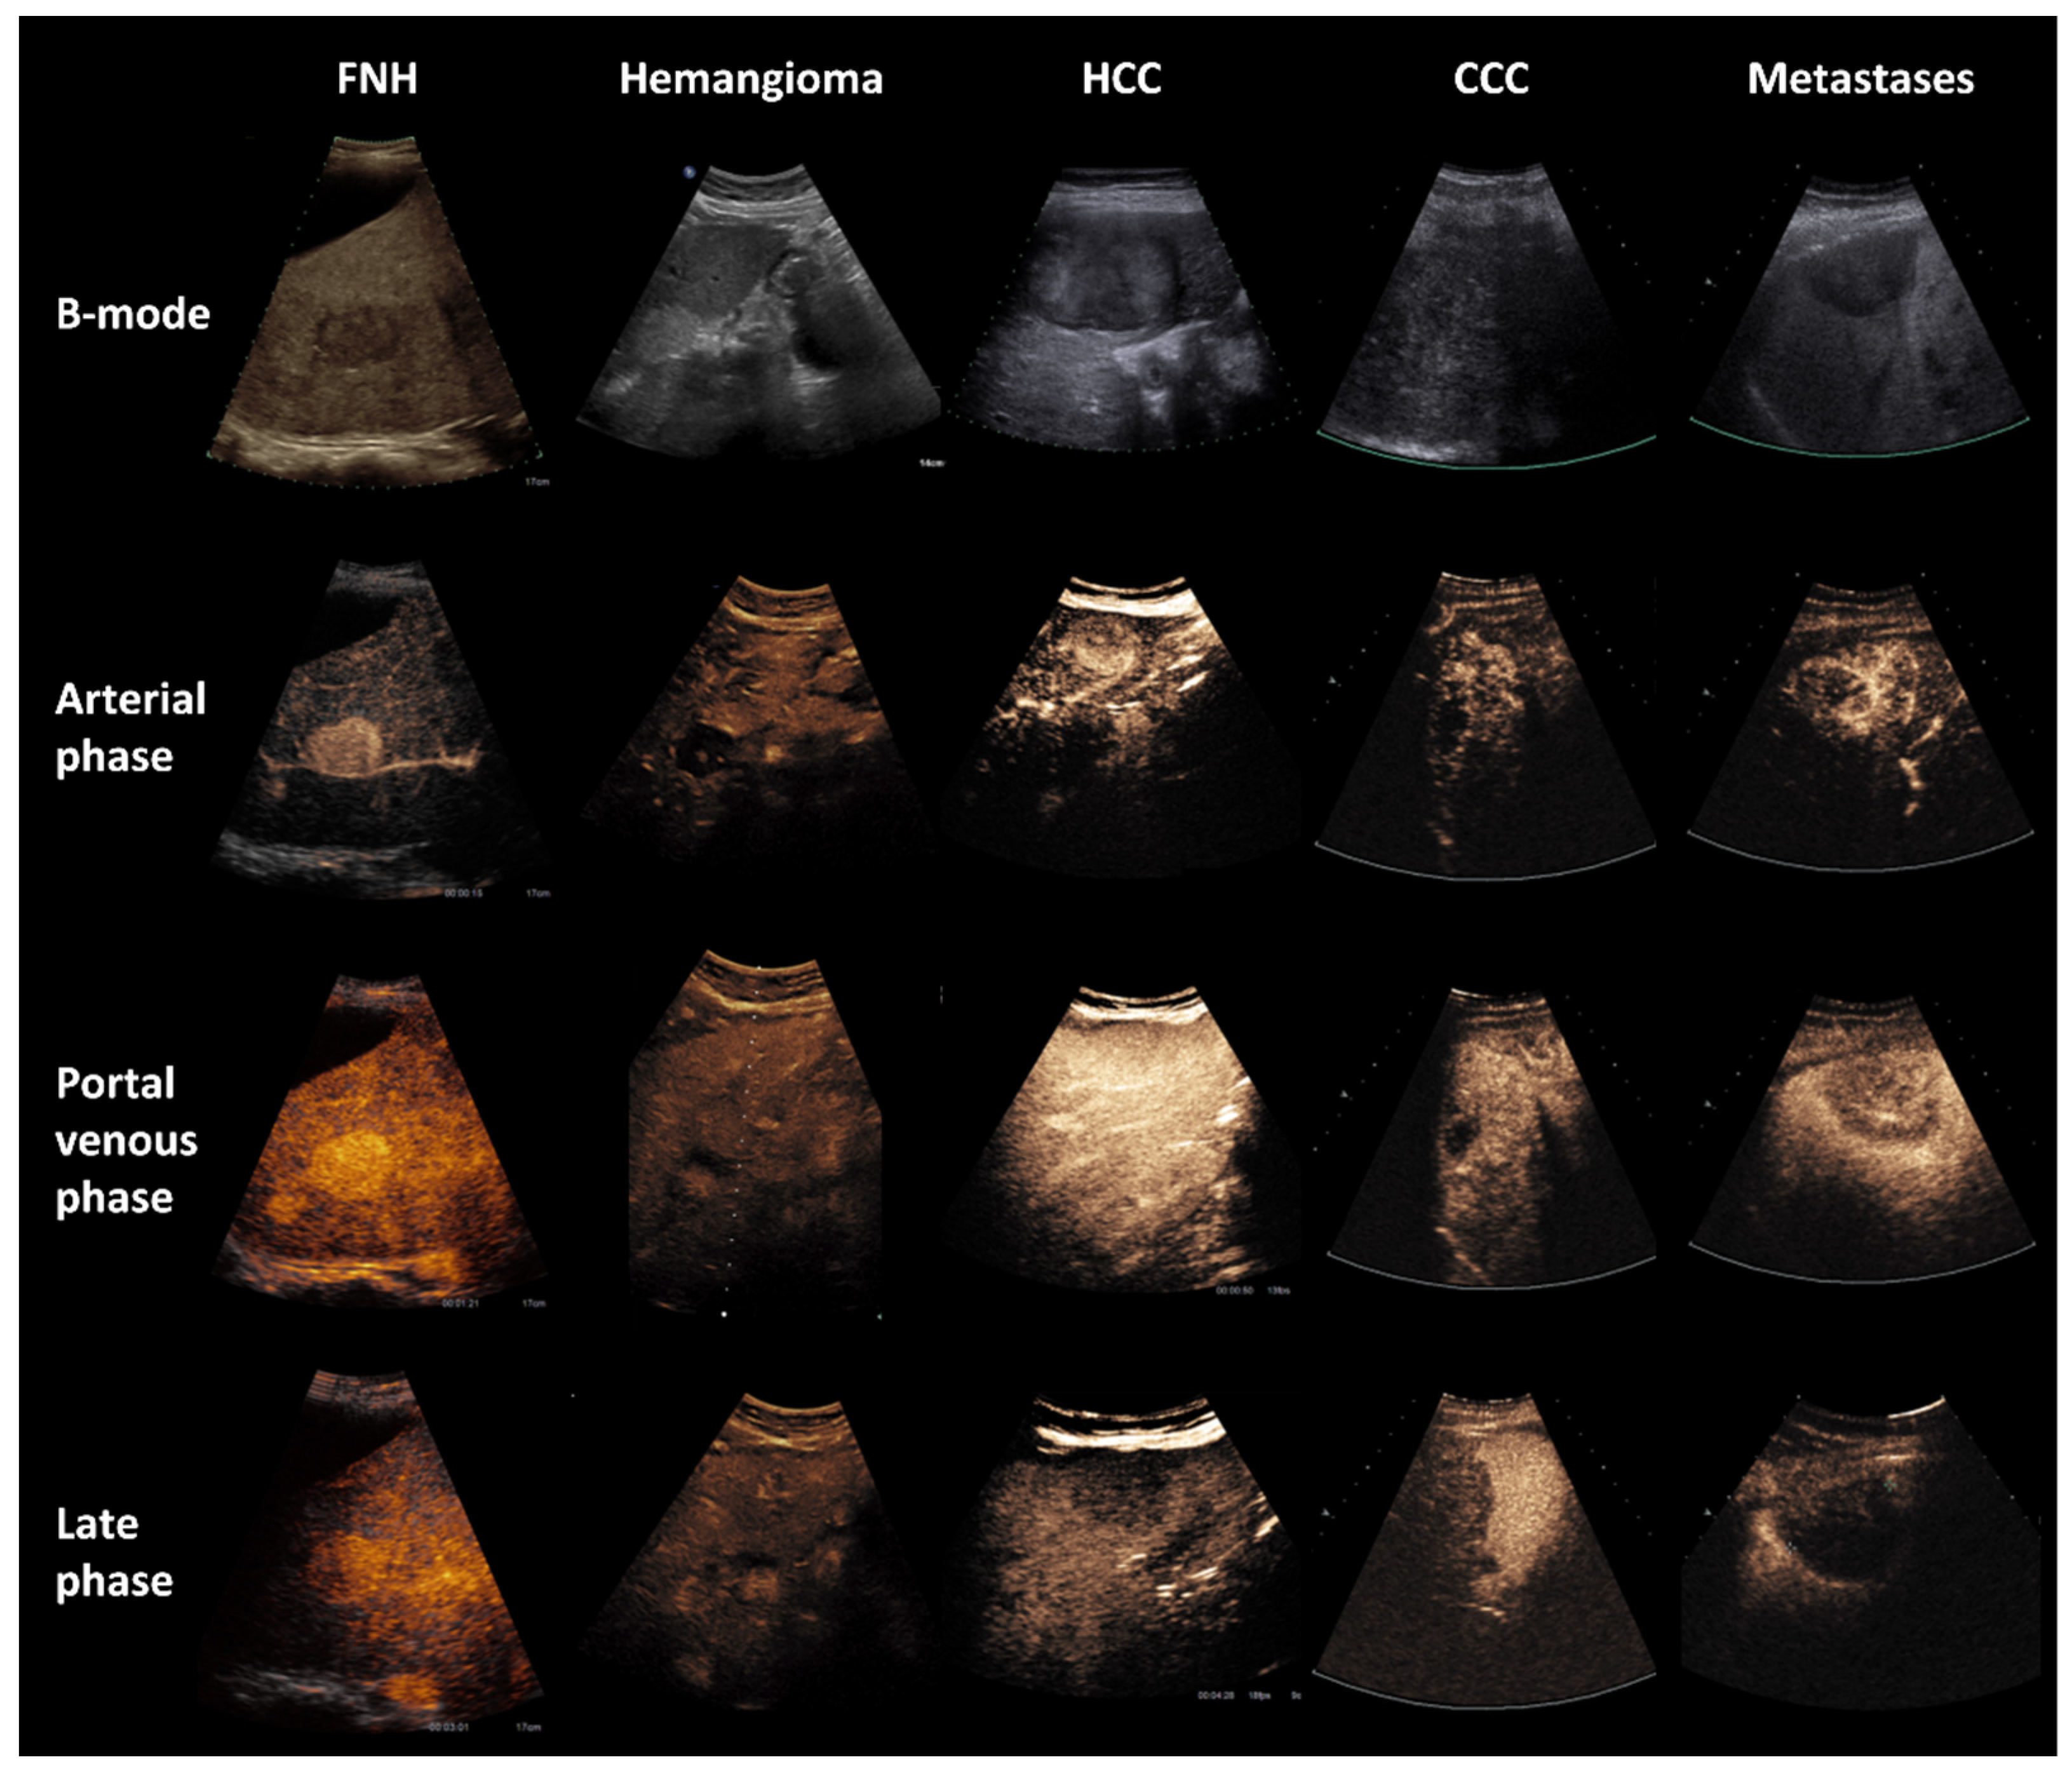

2.2. CEUS

3. Results